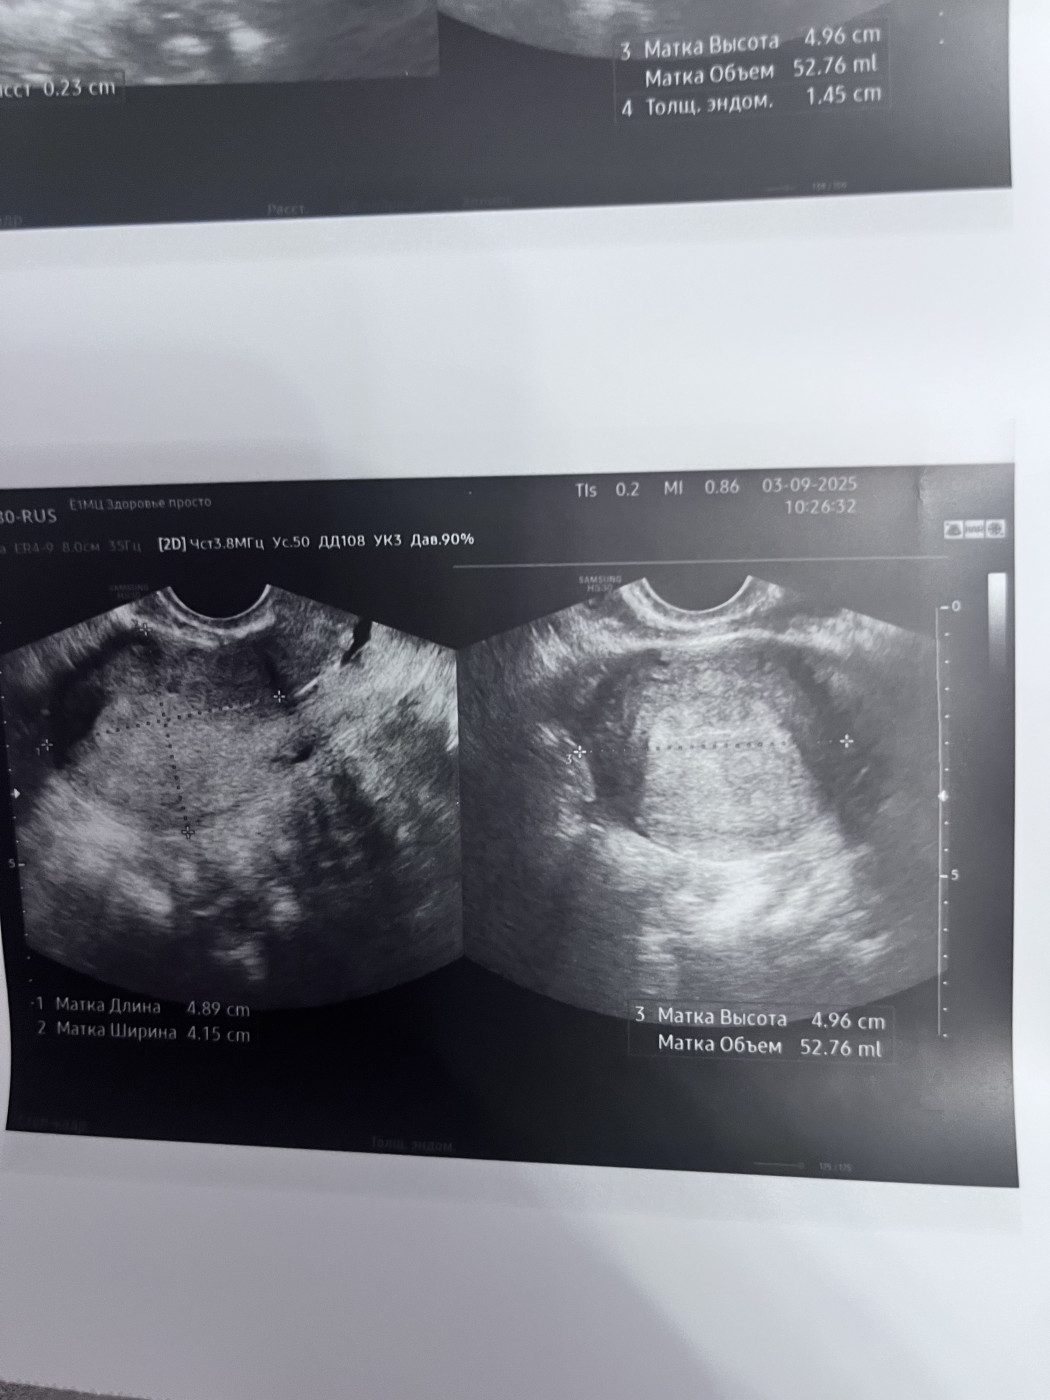

Результаты УЗИ

Размер матки